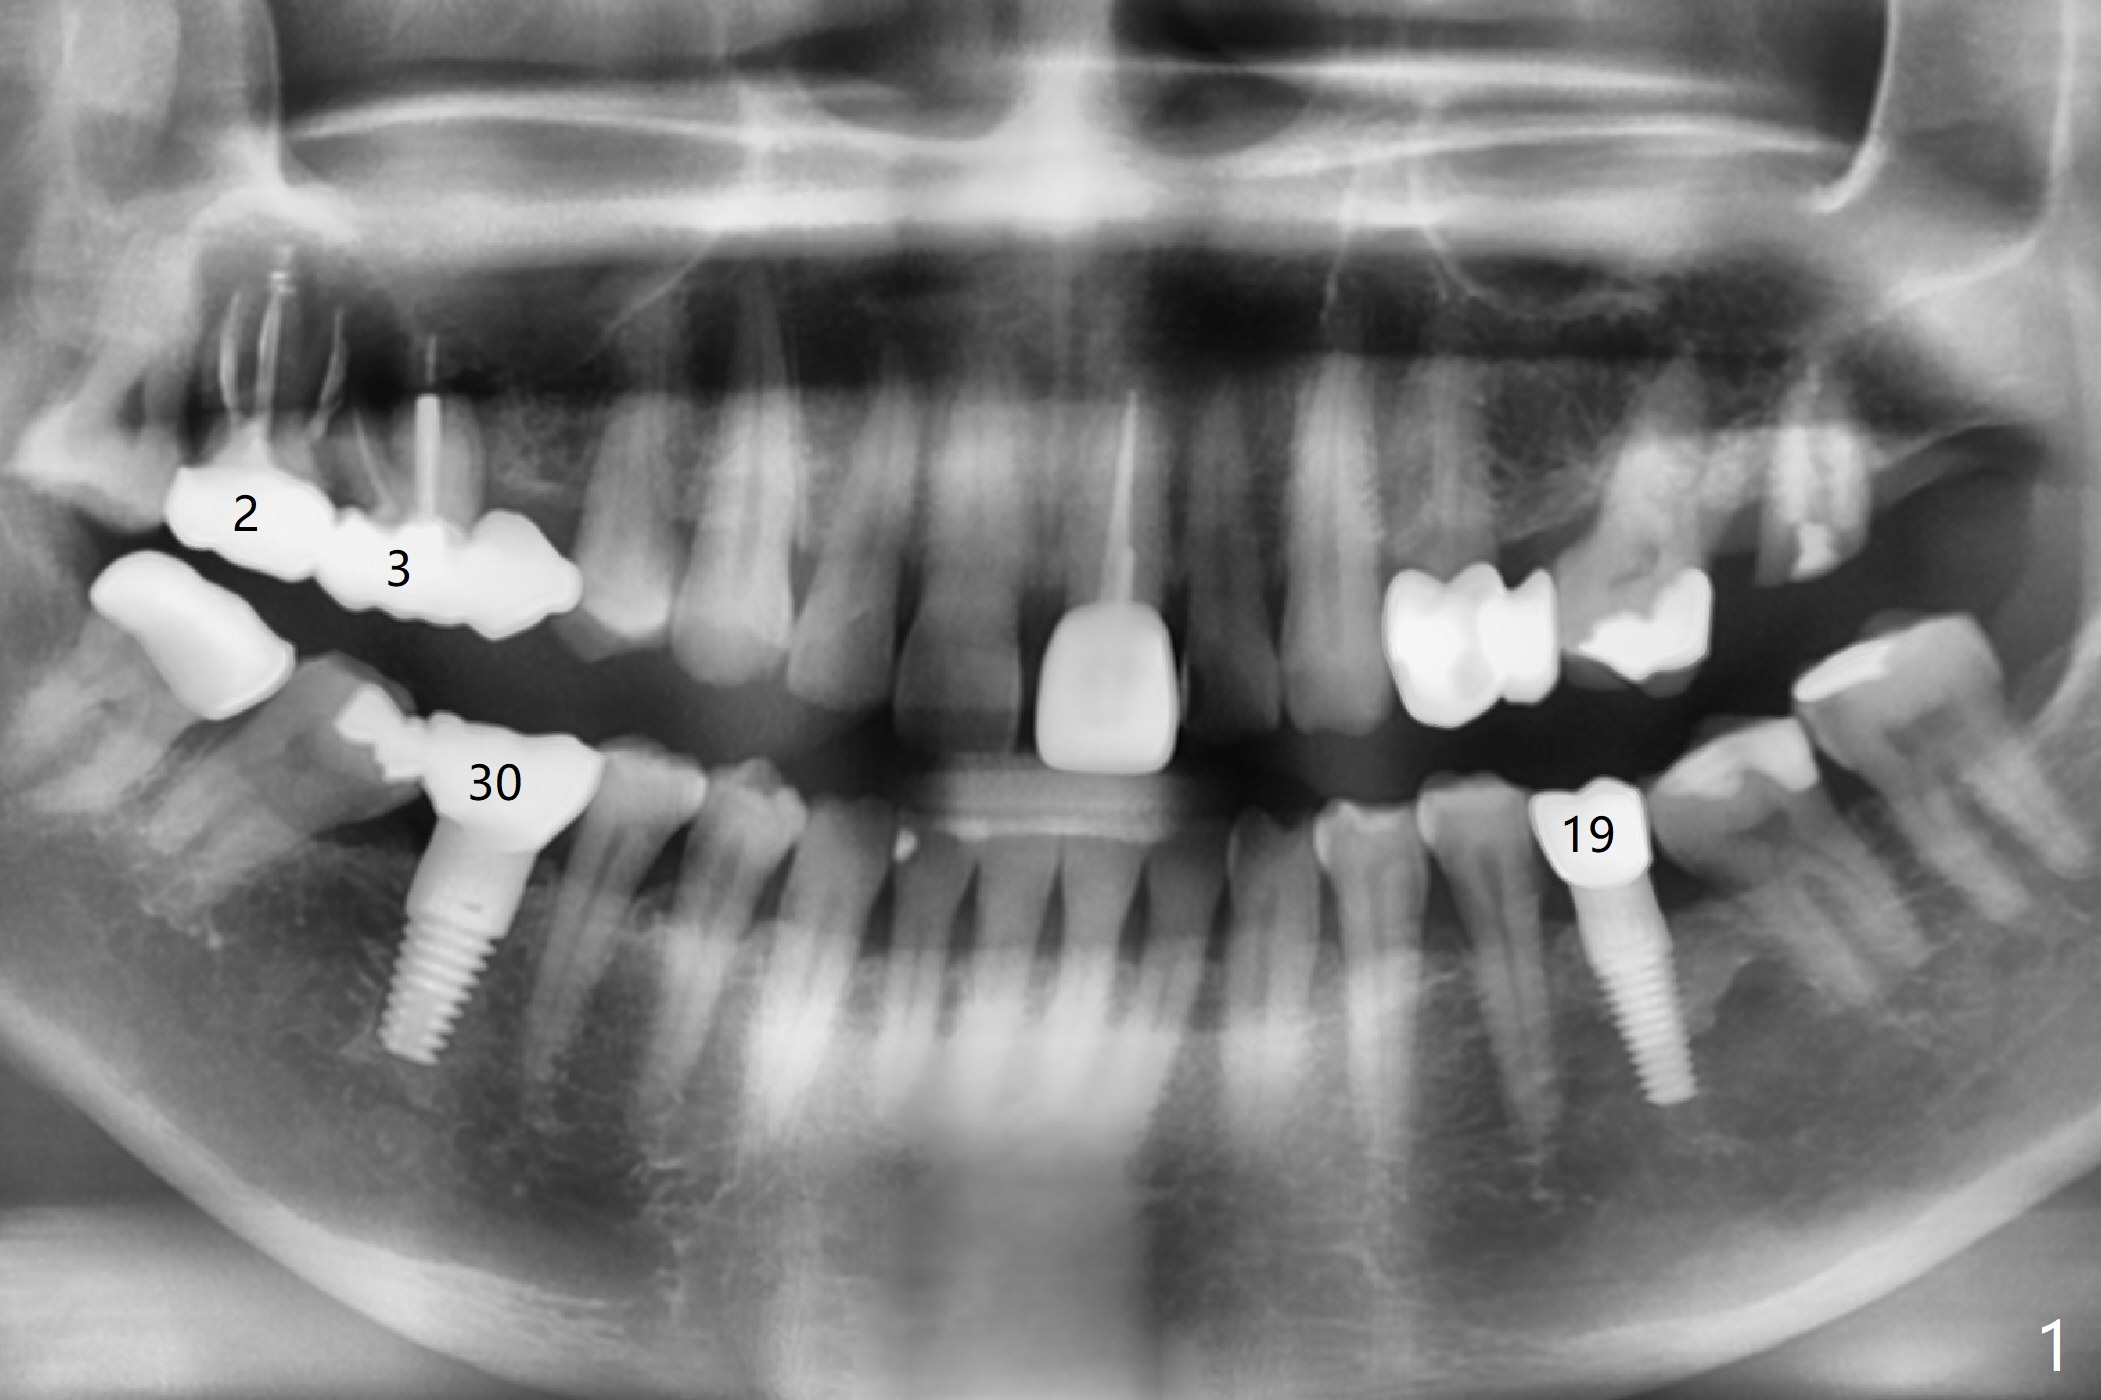

A 57-year-old woman returns with pain in the upper right quadrant (Fig.1,2). In fact the mesiobuccal root of the tooth #2 has vertical fracture. Although the socket destruction at #3 is not as extensive as that of #2, the socket of #3 has communication with the sinus. Prior to socket preservation, a piece of Osteogen plug is inserted at #3. PRF should be prepared for severe bone loss. In contrast there is no bone loss around the implants at #19 or #30 (Fig.1,3,4). Although the socket at #2 is slightly open 9 days postop, bone graft appears to be present (Fig.5). The bone at #2 and 3 seems to regenerate 7 months post socket preservation (Fig.6). Three short implants seem to be better than 2 implants for 3-unit FPD (Fig.7-9).